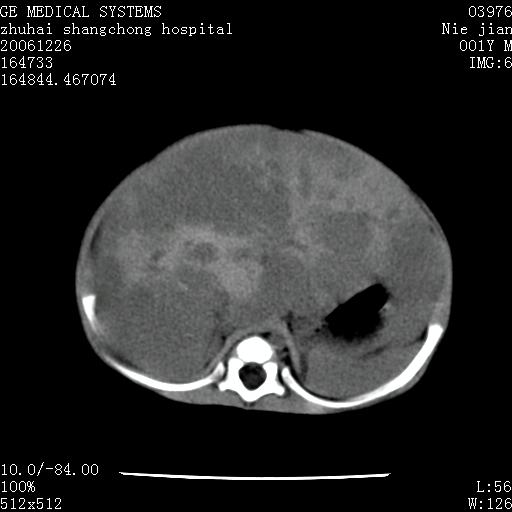

3个月婴儿腹胀来看。

肝各叶比率失调,明显增大,实质内大量脂肪侵润。另:左侧肾上腺区较大类圆形低密度肿块,左肾明显受压 下移。多考虑:1 左侧肾上腺神经母细胞瘤!2 肝弥漫性损伤!

肝各叶比率失调,明显增大,实质内见多发团块状低密度灶。另:左侧肾上腺区较大类圆形肿块,左肾明显受压 下移。多考虑:1 左侧肾上腺神经母细胞瘤!2 肝脏多发转移!

鉴别诊断:肾母细胞瘤,好发1-3岁,肾母细胞瘤是发生在肾脏,又称肾胚瘤,肾脏本身增大。而神经母细胞瘤也称成神经细胞瘤,好发1-2岁,多发生在肾上腺髓质。肾脏本身表现受压向下移位。

【影像特征】

1、肝明显增大,肝弥漫性低密度灶。

2、肾上腺区见类圆形肿块,其内密度不均,见片状偏高密度。

1、肝弥漫性病变,考虑急性肝炎致广泛脂肪浸润可能性大。

2、肾上腺区占位,假性肿瘤?肾上腺血肿(感染所致)?

1、关键着眼点:肝脏弥漫性病变内有没有走形的血管,仔细看部分低密度内有血管影(要有增强扫描作为证据就好了),说明并非肿瘤样病变,而是脂肪浸润。即可能不是转移瘤或原发肿瘤,低密度的形态上看,是片状,也不像肿瘤。

2、儿童肝炎最常见的是感染,有时食入性损害或药物也可致肝脏炎症,肝炎致大空泡型脂肪变性,是一种无痛性疾病,无症状,病因有营养异常、代谢性疾病、药物及病毒感染。所以脂肪变性与感染有关。

3、肝炎的结局是肝硬化,而恰恰一年后复查,已有肝硬化表现。肿瘤一般那会消失,那叫奇迹。

4、肾上腺出血也可见于败血症及感染,通常包块在数周内消失,ct表现包块内有偏高密度,可能是亚急性血肿的表现。假性肿瘤即腹部肠管积液、扩张血管及邻近结构的伪像。自然会消失。

5、因此,感染可以贯穿一切,解释一切。肿瘤自然消退?可能吗?那些应要无道理的创造奇迹的事情会那么容易发生吗?